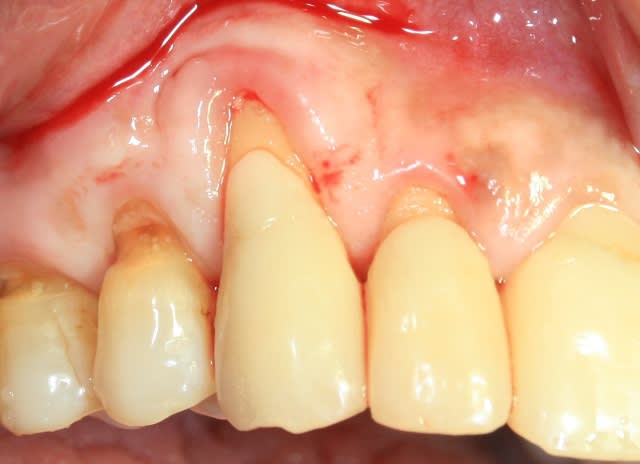

J'ai essayé cette technique suite à un échec d'un greffon conjonctif par tunnelisation sans doute par manque d'expérience et patiente fumeuse.

Cette fois ci lambeau pleine épaisseur GEN40 ( GEN-OSS) membrane de chez IDI.

En fait christophe, si tu regardes ta photo du départ tu avais de la gencive attachée(au dessus de ton bourrelet) et ton intervention a consisté à tracter cette gencive attachée sur ta récession ni plus ni moins.

Le but de cette chir était de rattraper une recession iatrogène et de recréer au niveau de la 13 une épaisseur gingivale satisfaisante pour la réalisation ultérieure de procéra.( c'était le cahier des charges de la 1° intervention qui a échouée ; lors de la création de la poche en mésial de la 13 la partie non travaillante de la lame a cisaillé à mon insu la fine gencive vestibulaire de la 13 et créée une cata)

La vitalité, le bourgeonnement, la vascularité à 10 jours me semblent satisfaisant.

Effectivement j'ai été un peu trop timoré et j'aurais du recouvrir plus large pour traiter également la 12.

Le GEN 40 est un peu trop visqueux et j'aurais du le mélanger avec un Gen Oss ou un Bio oss.

Ce qui n'apparait pas sur la photo initiale , c'est une très importante concavité-dépression entre 13 et 12 ( qui explique la galère lors de la tunnélisation ) mais je n'ai pas fait de photos en vue occlusale.